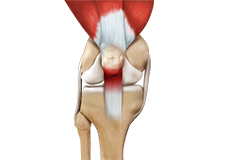

Patellar Instability

Any damage to the supporting ligaments may cause the patella to slip out of the groove either partially (subluxation) or completely (dislocation).

Patellofemoral Instability

Any damage to the supporting ligaments may cause the patella to slip out of the groove either partially (subluxation) or completely (dislocation). This misalignment can damage the underlying soft structures such as muscles and ligaments that hold the kneecap in place.

Patellar Dislocation/Patellofemoral Dislocation

Patellar dislocation occurs when the patella moves out of the patellofemoral groove, (trochlea) onto the bony head of the femur. If the kneecap partially comes out of the groove, it is called subluxation; if the kneecap completely comes out, it is called dislocation (luxation).

Patellar Tracking Disorder/Patellar Maltracking

Patellar tracking disorder, also known as patellar maltracking, is a condition in which the kneecap (patella) moves sideways from its groove when the leg is bent or straightened.